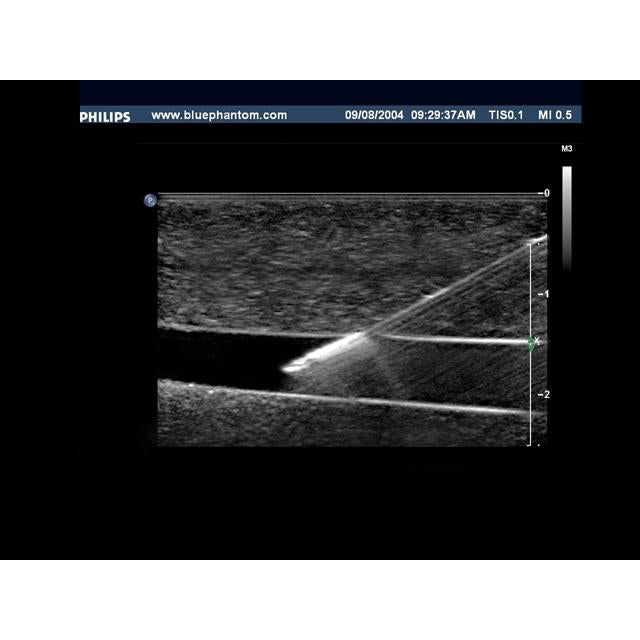

Our Branched 4 Vessel ultrasound guided vascular access training model contains a blood vessel that branches into 4 vessels positioned at differing depths and course throughout the model. Users can image the bifurcating vessels, track the course of the vessels, and guide needles into the targeted vessel using ultrasound imaging. Clinicians can gain experience acquiring and interpreting ultrasound images of blood vessels as well as developing the psychomotor skill associated with guiding needles to simulated vessels.

Our Branched 4 Vessel ultrasound guided vascular access training model contains a blood vessel that branches into 4 vessels positioned at differing depths and course throughout the model. Users can image the bifurcating vessels, track the course of the vessels, and guide needles into the targeted vessel using ultrasound imaging. Clinicians can gain experience acquiring and interpreting ultrasound images of blood vessels as well as developing the psychomotor skill associated with guiding needles to simulated vessels.

Excellent ultrasound imaging characteristics.

Gain experience by choosing to guide needles to individual vessels or for more advanced training, target overlapping branched vessels at different depths as you would experience in the human patient. Once users accurately access the vessels within the model, fluid flow provides the user with positive feedback that they have accessed the targeted vessel.

Excellent ultrasound imaging characteristics.

Gain experience by choosing to guide needles to individual vessels or for more advanced training, target overlapping branched vessels at different depths as you would experience in the human patient. Once users accurately access the vessels within the model, fluid flow provides the user with positive feedback that they have accessed the targeted vessel.